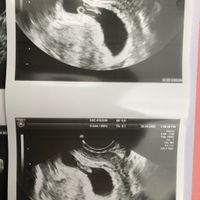

Ciaooo qualcuna ha sentito parlare del metodo Ramzi? A voi ci ha azzeccato o ha sbagliato? Vi metto una foto dell’eco interna a 7+3 “dovrebbe” essere maschio secondo la teoria o sbaglio io a vedere?...

Qualcuna che se ne intende? Io di angoli non ho capito nulla provate a indovinare , forse il 23 agosto riuscirò a vedere il sesso e vi dirò se avete indovinato!!! !